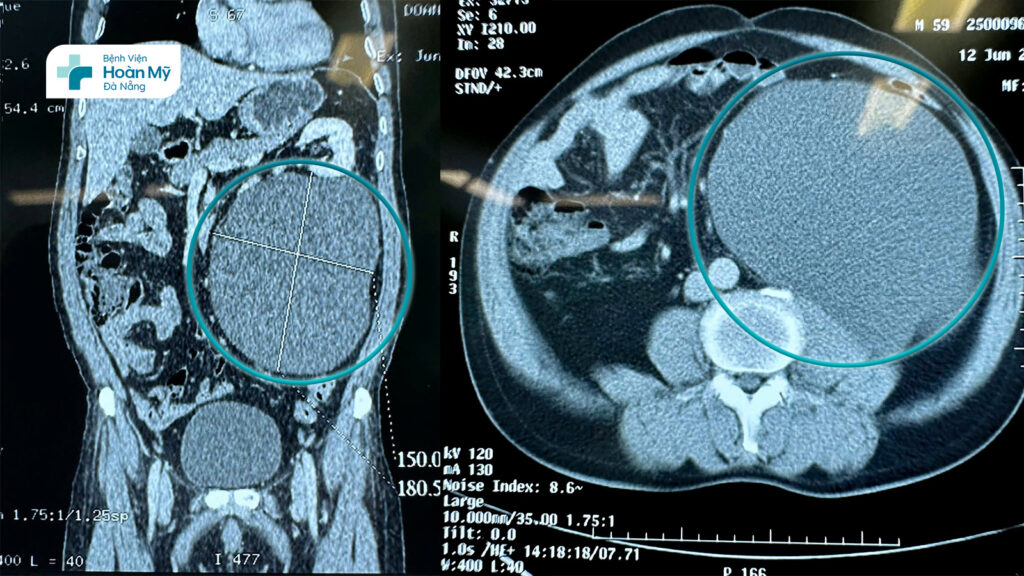

(hình 1) Hình ảnh chụp CT cho thấy khối u nang lớn chèn ép nội tạng

Xác định phải phẫu thuật, người bệnh tìm đến Bệnh viện Hoàn Mỹ Đà Nẵng. Tại đây người bệnh được thăm khám lâm sàng và cận lâm sàng để đánh giá lại thêm 1 lần nữa. Mặc dù đây là khối u có kích thước lớn nhưng các xét nghiệm máu và chẩn đoán hình ảnh hướng tới một khối u nang sau phúc mạc lành tính (hình ảnh CT Scan cho thấy một khối dạng nang 150 x 180 mm, ranh giới rõ, đè đẩy các tổ chức xung quanh, dịch đồng nhất và không ngấm thuốc cản quang), thể trạng người bệnh tốt, vì vậy các bác sĩ chỉ định phương pháp phẫu thuật nội soi sau phúc mạc bóc toàn bộ khối u làm giải phẫu bệnh lý.